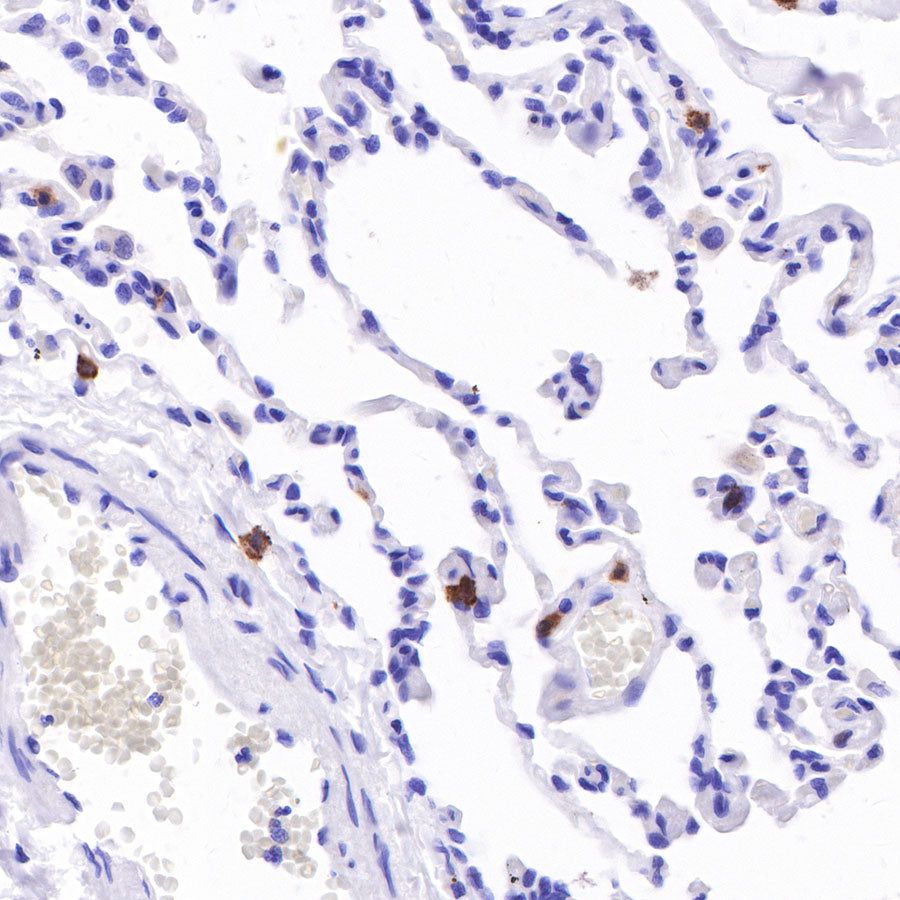

IHC shows positive staining in paraffin-embedded human pancreatic cancer. Anti-CD103 antibody was used at 1/100 dilution, followed by a HRP Polymer for Mouse & Rabbit IgG (ready to use). Counterstained with hematoxylin. Heat mediated antigen retrieval with Tris/EDTA buffer pH9.0 was performed before commencing with IHC staining protocol.